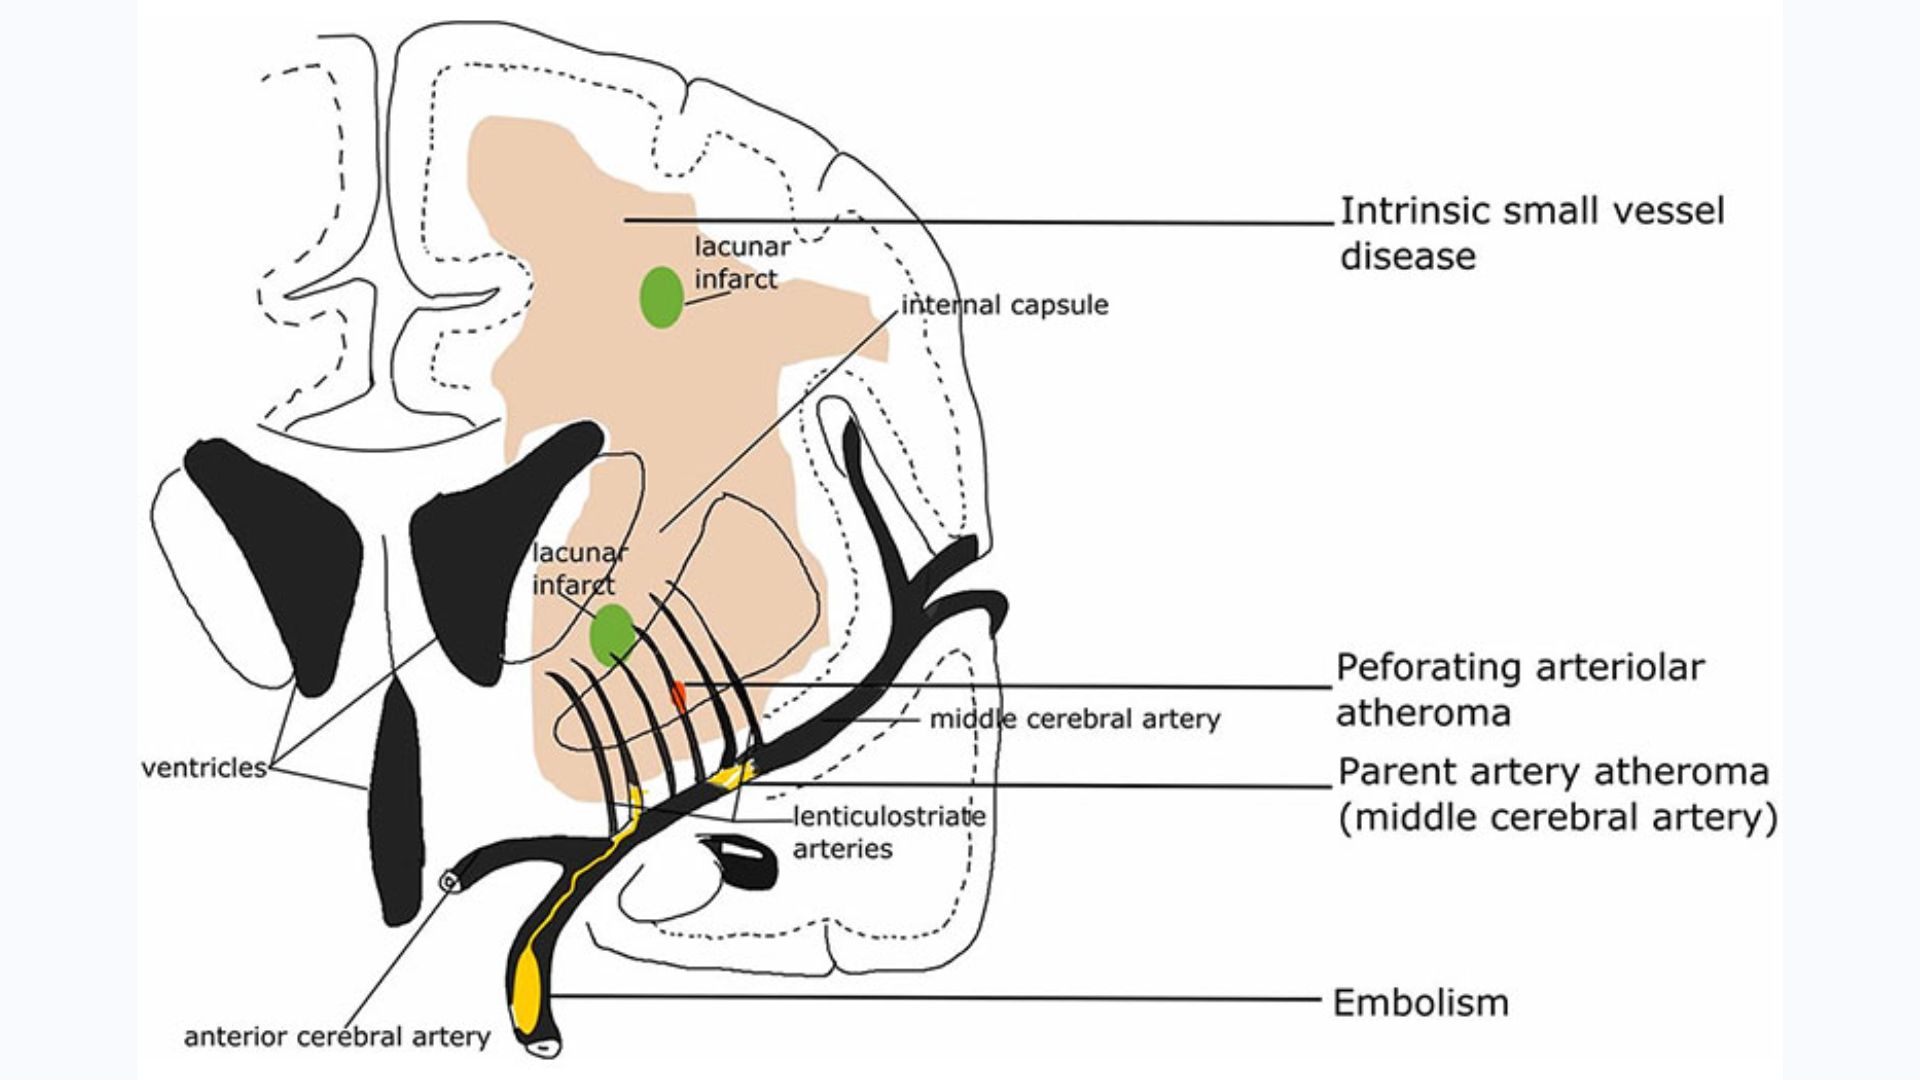

Nhồi máu não lỗ khuyết là những ổ tổn thương nhỏ dưới vỏ có đường kính dưới 15mm do tắc các tiểu động mạch hoặc động mạch xiên (penetrating arteries) là những nhánh tách trực tiếp từ các động mạch não lớn, thường gặp nhất là từ đa giác Willis, động mạch não giữa và động mạch nền.

Các động mạch xiên là những mạch máu có kích thước nhỏ hơn 0.5mm đường kính, kích thước của một ổ nhồi máu tối đa từ 0.5 – 15mm tương đương với một thể tích 0.2 – 2ml. Cần lưu ý rằng không phải tất cả các nhồi máu nhỏ ở sâu đều là nhồi máu ổ khuyết. Chẩn đoán nhồi máu ổ khuyết đòi hỏi phải loại trừ các nguyên nhân nhồi máu não khác.

Nhồi máu não lỗ khuyết xảy ra khi mạch máu cung cấp cho các cấu trúc sâu bên dưới não đột ngột bị tắc, gây ra những tổn thương nhỏ trong não. Yếu tố nguy cơ quan trọng nhất là huyết áp cao mạn tính. Tình trạng này có thể khiến mạch máu bị thu hẹp. Từ đó, các mảng cholesterol hoặc cục máu đông dễ dàng gây tắc dòng máu đến các mô não sâu.

Khu trú lỗ khuyết thường gặp là nhân bào (37%), đồi thị (14%), bao trong (10%), cầu não (36%), vành tia, bao ngoài, bó tháp và các cấu trúc khác của thân não. Thường gặp khoảng 18-40% bệnh nhân trước đó đã bị các cơn thiếu máu não cục bộ tạm thời. Các triệu chứng có thể xuất hiện đột ngột hoặc từ từ, các thiếu hụt thần kinh tiền đình chậm trong 2-3 ngày và xuất hiện xuất huyết nhỏ mà chụp cắt lớp vi tính (CT-scanner chỉ phát hiện được 2/3 trường hợp, còn chụp cộng hưởng từ (MRI) có khả năng chẩn đoán với tỷ lệ cao hơn.